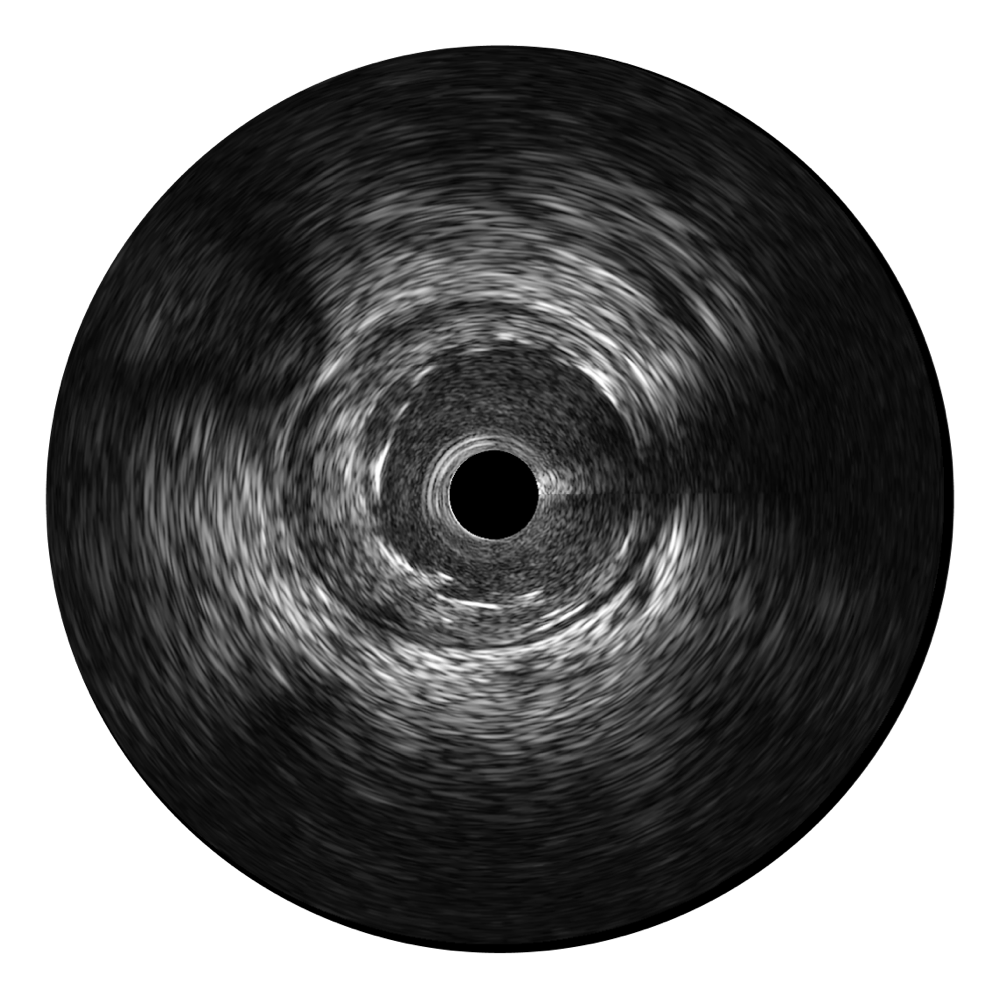

新葡的京集团8814检测站超宽频成像技术覆盖20-80MHz1或20-90MHz2频率范围, 提供优异的分辨力同时也保证充足的穿透深度

对比传统IVUS导管成像,新葡的京集团8814检测站宽频IVUS图像的近场支架梁显影更细腻,远场中膜外血管仍清晰可辨,兼顾远中近,兼顾分辨力与穿透深度